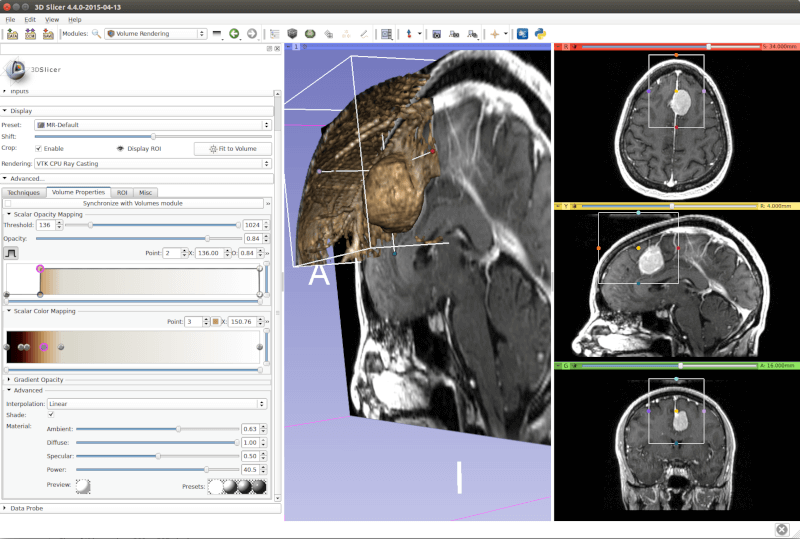

8. 3D Slicer

3D Slicer is a feature-rich multi-platform integrated application for processing images, medical image informatics, and 3D visualization intended for clinical researchers, physicians, and computer scientists.

You can use 3D slicer for sophisticated manual editing, automatic segmentation, analysing and visualizing diffusion tensor imaging data, reading and writing DICOM images and other formats, batch processing using EMSegment BatchMake e.t.c filtration, among many other functions.